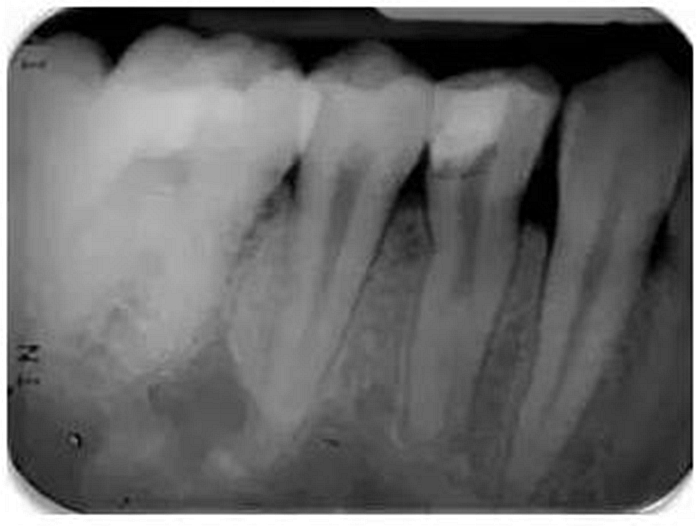

根尖周X線片必須要有最小的失真率和放大倍率,因?yàn)槿魏紊扉L和透視縮短都會(huì)導(dǎo)致根管長度測量的錯(cuò)誤。對(duì)牙根進(jìn)行仔細(xì)的評(píng)估是必不可少的,因?yàn)榭赡苡谢窝栏▓D1)。在中國患者中發(fā)現(xiàn)C形根管或其他蒙古人種特征的畸形牙根和根管是很常見的。因此,對(duì)X線片進(jìn)行全面評(píng)估以確定是否存在額外的牙根或根管是必要的,由此我們可以判斷治療的難度系數(shù)。